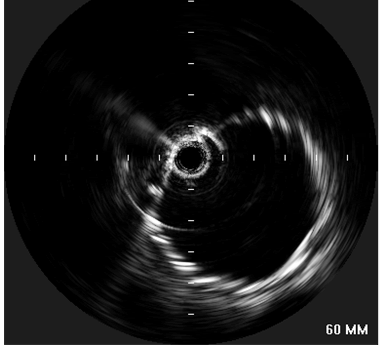

Informed consent was obtained and the patient was offered endovascular repair of the contained aortic rupture using the Medtronic Talent endoprosthesis through a single institution Investigator Investigational Device Exemption (IDE) approved by the FDA. In the endovascular suite, the patient was placed in supine position and underwent local anesthesia with sedation. The left common femoral artery was exposed and then accessed using an 18-gauge needle and a 0.035 inch flexible-tipped Bentson Starter guidewire was passed in a retrograde fashion into the descending aorta under fluoroscopic guidance. 3000U of Heparin was administered and a 14-Fr introducer sheath was placed in the left common femoral artery. The IVUS (Volcano Visions, PV 8.2 F) catheter was used to guide and advance the Starter guidewire safely across the contained rupture area into ascending aorta. Upon advancement of the IVUS probe into the thoracic aorta, the area of transection was encountered. There was a dissection flap with a dilated and disrupted area in the middle of aorta

| Figure 3: IVUS showing the site of aortic rupture. |

(Figure 3). The proximal aspect of the transection was 1.5 cm below the origin of the left subclavian artery. Origins of the arch vessels were marked on the masked picture on the fluoroscopy monitor. Using the IVUS, the aortic diameter was measured 28 mm just distal to the left subclavian artery and 29 mm at origin of the left common carotid artery. It was decided to cover the left subclavian artery to get an adequate landing zone for the endoprosthesis. Therefore, the IVUS was placed just distal to the left carotid artery and its position marked on the fluoroscopic screen. The catheter was then withdrawn until above, and then below the transected area. These measured 36 mm and 76 mm in length, respectively. With these measurements in mind, a 30 mm diameter by 130 mm in length Medtronic Talent device with 15 mm proximal wire configuration was selected to exclude the transected portion of the aorta.